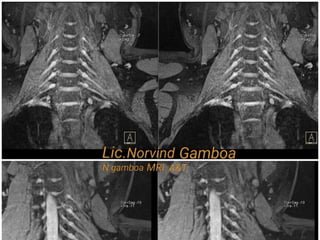

Evaluación del LCA en plano oblicuo

coronal en cual evaluamos ambas

inserciones.

La inserción próximal se encuentra en una

fosa en la faceta posterior de la superficie

medial del condilo femoral lateral y la

insercion distal se encuentra en la fosa

frente de Y lateral a la espina tribial

anterior y pasa debajo del ligamento

meniscal transverso.

Se puede usar como plano único o en

complemento al plano oblicuo sagital al

LCA.